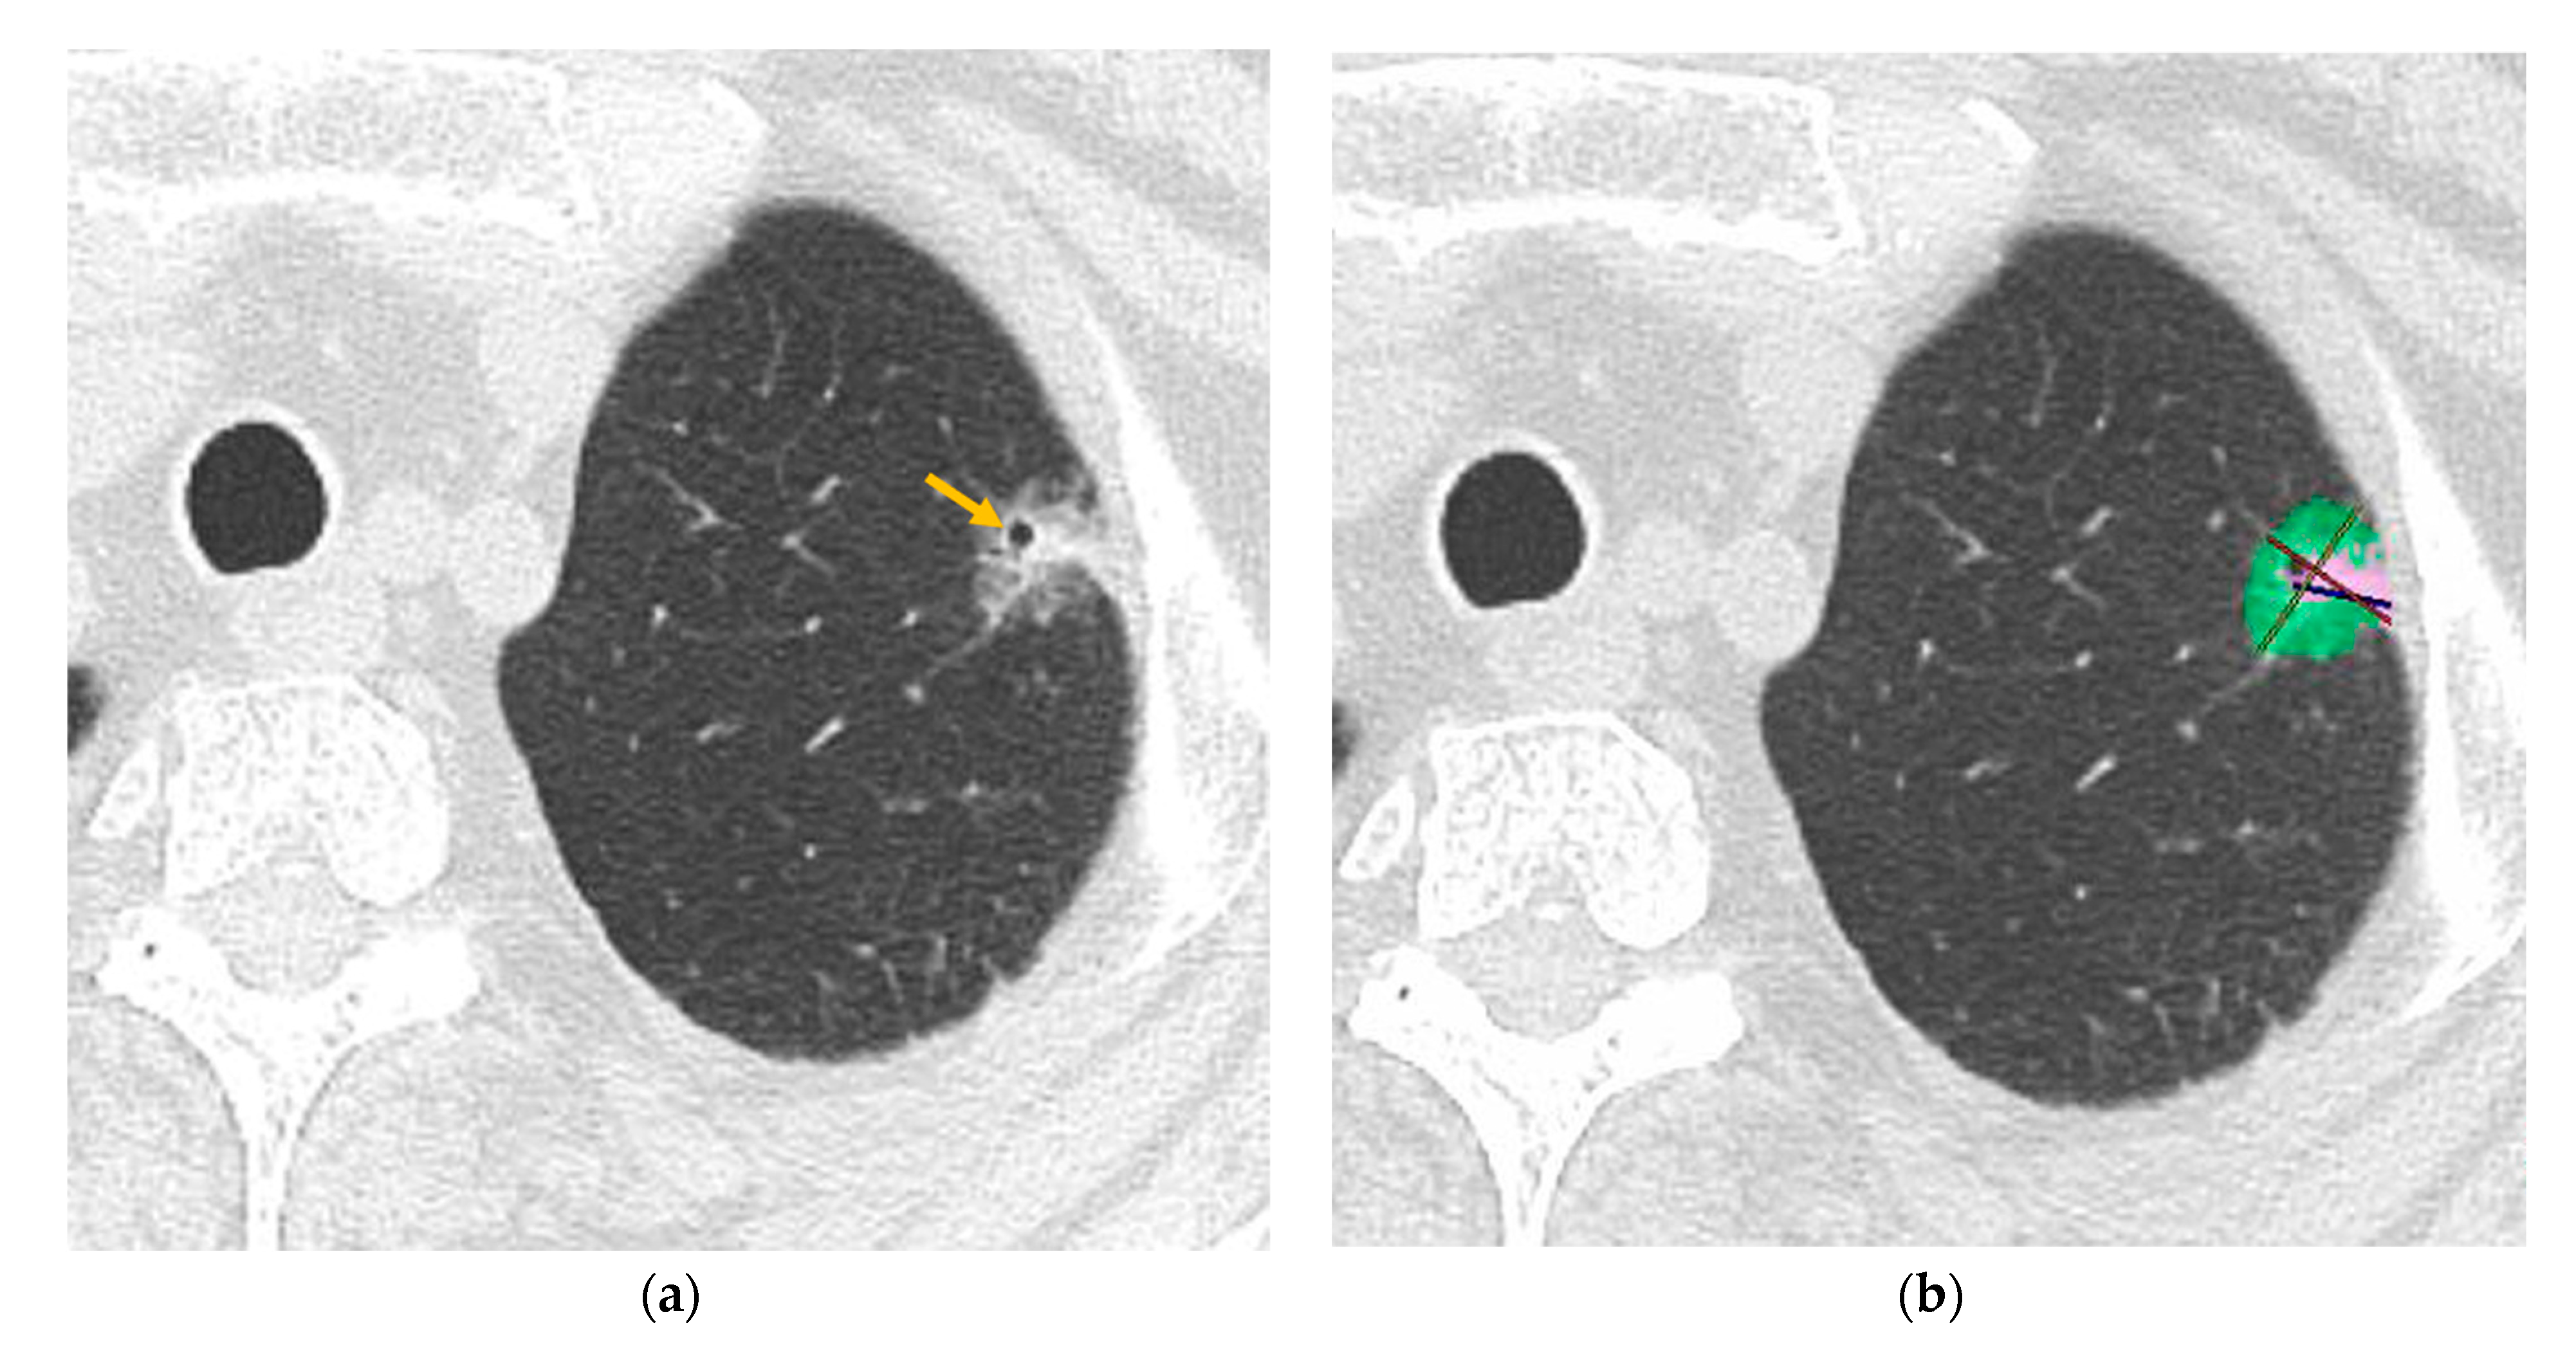

2.3. CT Analysis